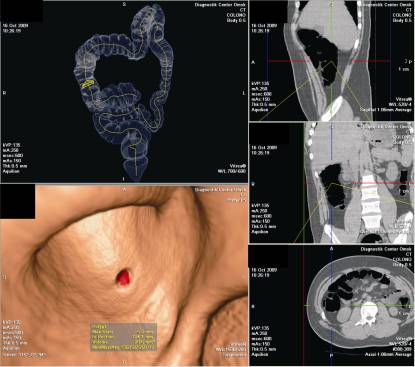

У 25 пациентов из исследуемой группы были

выявлены признаки колоректального рака (Рисунок 3).

Рисунок 3. Виртуальная

колоноскопия. Экзофитный рак купола слепой кишки.

образования толстой кишки (Рисунок 4).

Рисунок 4. Виртуальная

колоноскопия. Полиповидное образование восходящей кишки.